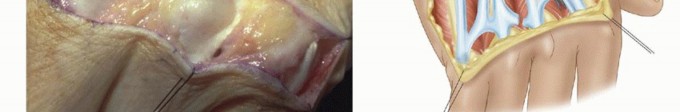

Intrinsic Release and Soft Tissue Balancing

Following the synovectomy, the joint must be assessed for passive correctability. The proximal phalanx is manually manipulated into neutral alignment (zero degrees of radial/ulnar deviation) and full extension. If resistance is encountered, or if the digit springs back into ulnar deviation upon release, an intrinsic muscle contracture is present and must be addressed.

The ulnar intrinsic tightness is evaluated using the intrinsic tightness test (Bunnell test). If the ulnar intrinsic muscles (the volar interossei and the abductor digiti minimi for the small finger) are contracted, an intrinsic release is mandatory. This is performed by identifying the oblique fibers of the ulnar intrinsic wing at the level of the proximal phalanx and sharply dividing them. In severe cases, a release of the ulnar collateral ligament from its metacarpal origin may be necessary to achieve full passive correction, though this should be done judiciously to avoid creating iatrogenic radial instability.

Figure 9: Execution of an ulnar intrinsic release. The oblique fibers of the ulnar intrinsic wing are identified and divided to alleviate the fixed deforming forces.